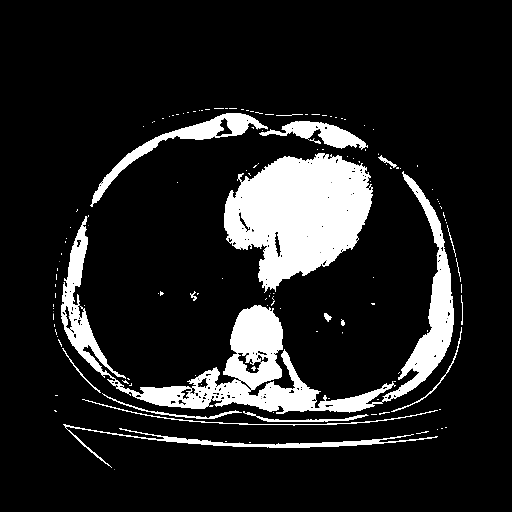

Generated VENOUS CT scan (A→B translation)

Full window (WL 1023.5, WW 4095 β†’ Low βˆ’1024, High +3071)

Actual HU range: [-1024.0, 3071.0]